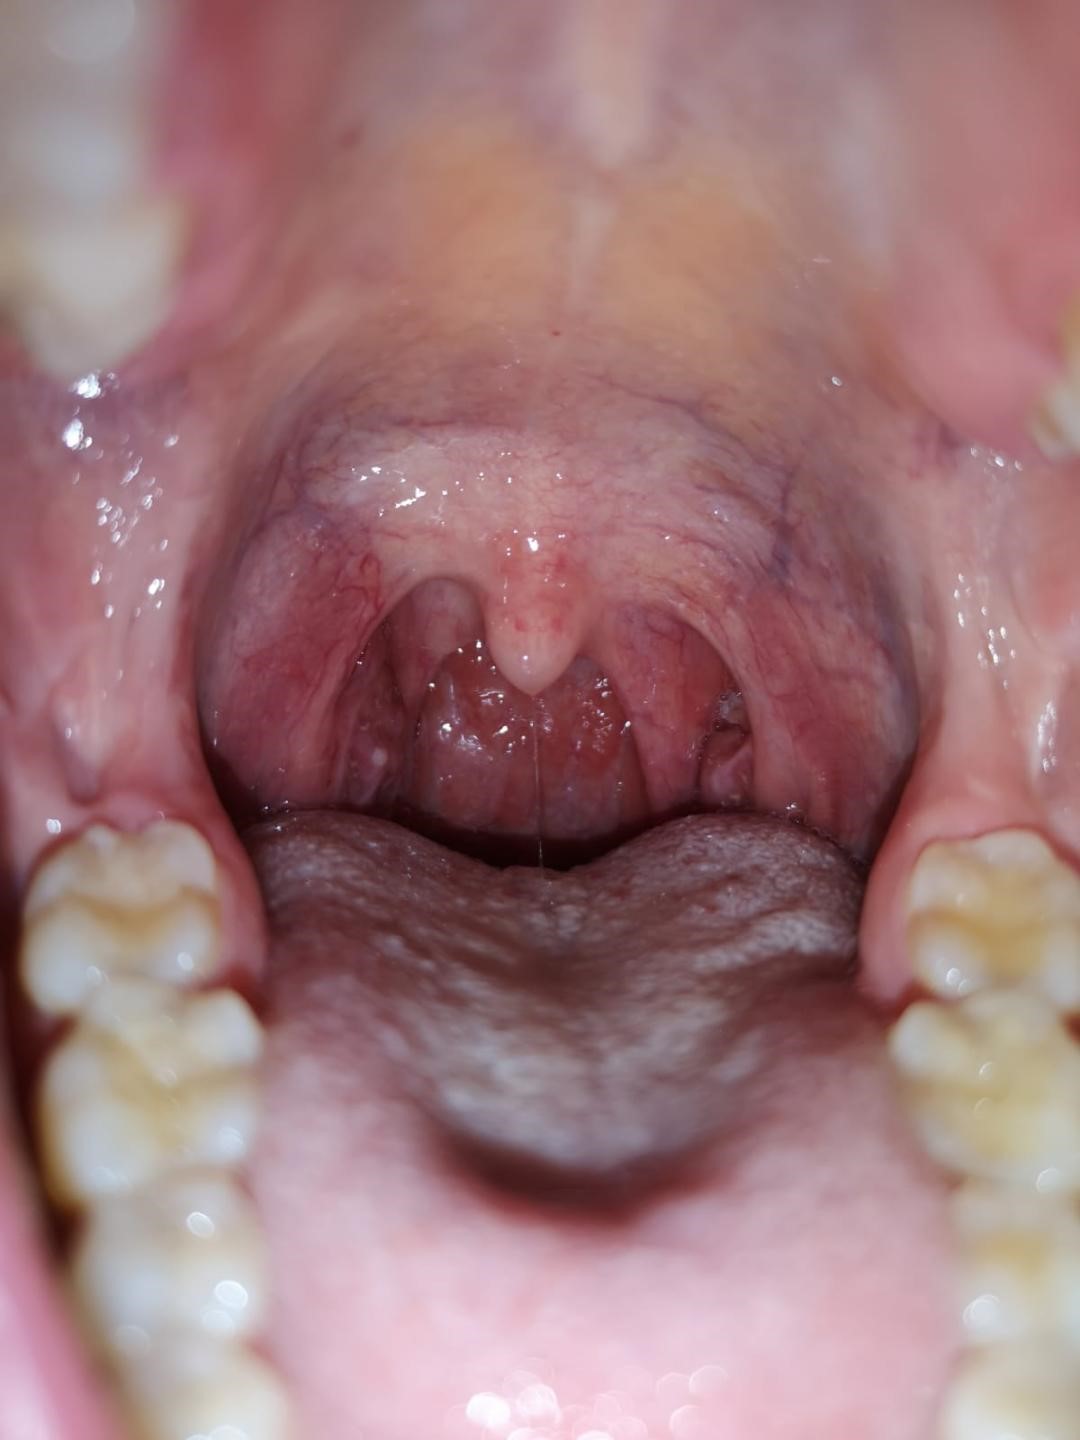

Poza 1- Status 5 zile posoperator ( se remarca prezenta de false membrane la nivelul ambelor amigdale palatine)